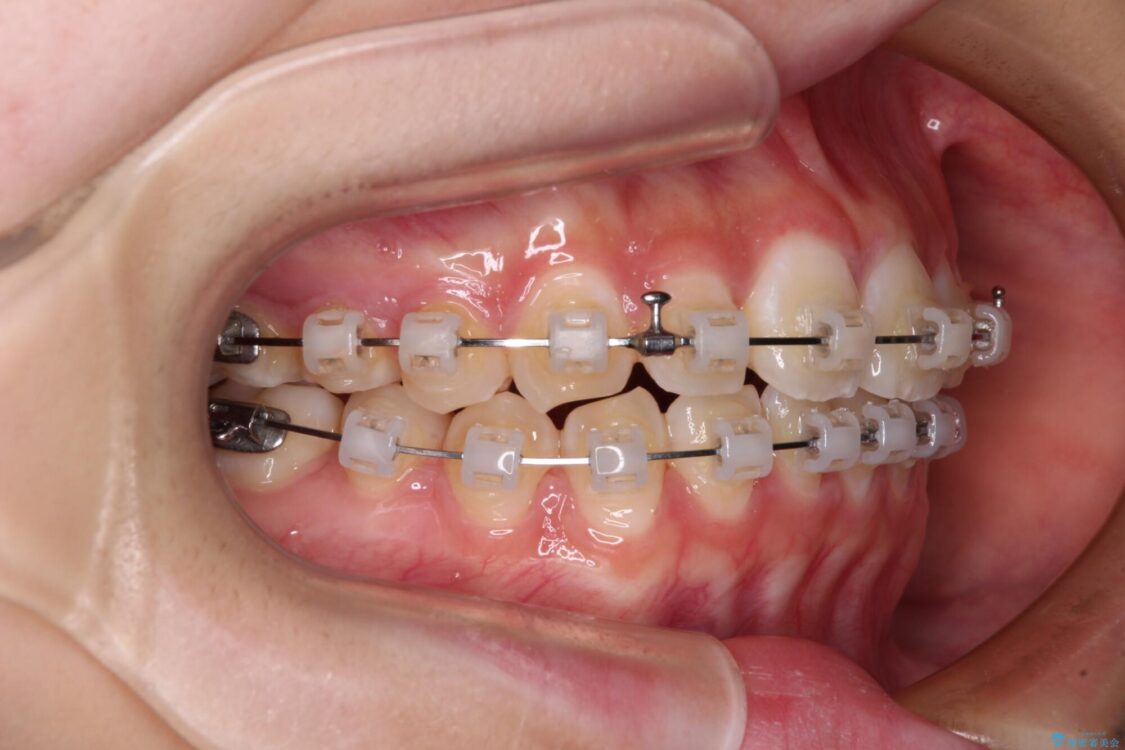

治療途中

• インビザラインは使える自信がない ワイヤー装置にて矯正治療 治療途中画像

ワイヤー矯正でもマウスピース矯正でも対応可能でしたが、マウスピース矯正の自己管理が面倒であること、上顎前歯の捻転が著しいことから、ワイヤー矯正での治療を希望されました。